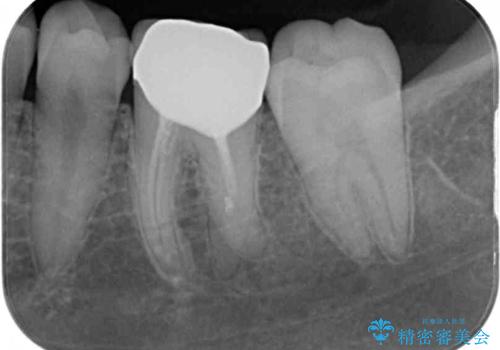

仮歯に置き換えた時点で希望に近い形態とできたので、その形を踏襲してオールセラミッククラウンを製作してもらいました。

気になっていた形が改善され、色調も自然なものとなったので、患者様には大変満足していただきました。